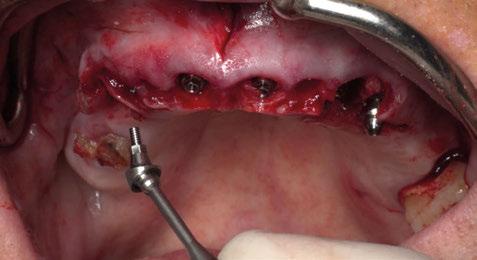

Figura 18. Procedimiento quirúrgico. a) customización de la lámina de cortical acorde a las características del defecto (Lámina de cortical desmineralizada Cortiflex® Salugraft Dental). b) fijación de la lámina cortical con microtornillos.

19.

y cierre del procedimiento quirúrgico. Vista vestibular/frontal.

Figura 20. Sutura y cierre del procedimiento quirúrgico. a) vista lateral/de perfil. b) vista oclusal.

Figura

Sutura

En este sentido, vuelve a realizarse el mismo protocolo de materiales que en el primer caso clínico. Es decir, en primer lugar se sutura un injerto de tejido conectivo al colgajo; posteriormente se utiliza un injerto óseo alogénico particulado (OraGRAFT® Aloinjerto Cortical Particulado MIX 70% Mineralizado / 30% Desmineralizado) para reconstruir la dehiscencia ósea además de preservar el escaso alveolo del diente extraído; y adicionalmente se utiliza la lámina de cortical desmineralizada (Lámina de cortical desmineralizada Cortiflex® Salugraft Dental).

La sutura realizada en este procedimiento quirúrgico es idéntica a la del primer caso clínico.